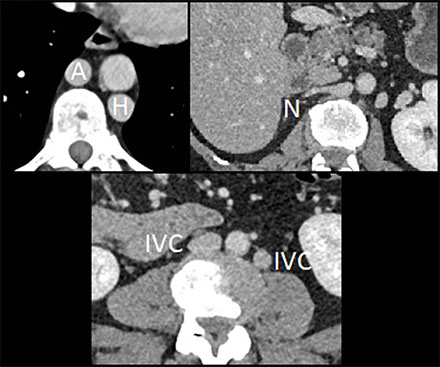

– Duplicated inferior vena cava system (IVC) with dilated azygos (A) and hemiazygos (H) continuation and no communication with hepatic veins (N) (Figure 2).